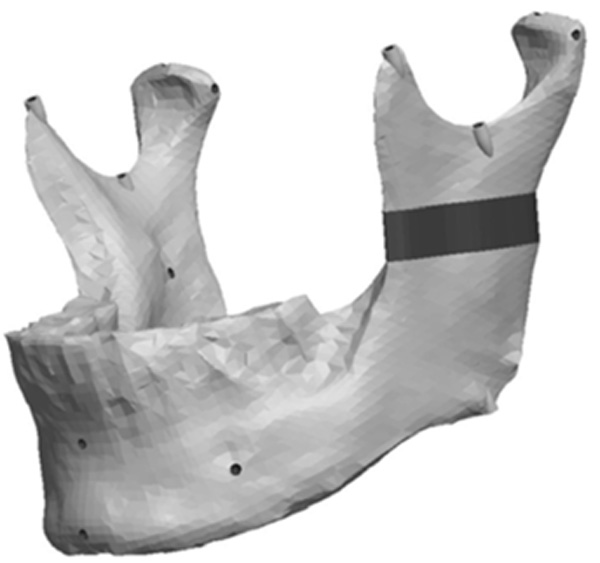

The Ramus section was located half way between the superior aspect of the condylar head and the depth of the antigonial notch. The location for the cut was determined by constructing a point half way between the most superior point on the condyle head (Cs) and the depth of the antigonial notch (Ag). A plane was selected perpendicular to the Cs-Ag line and plane MD which was used to guide the cut that penetrated through the neck of the condyle running parallel to the occlusal plane. Fig. (13) represents the location in the ramus of the mandible for the sections made to generate the ramus asymmetries. From this section, vertical and complex asymmetries were constructed in the ramal region. The vertical manipulation studied was to a maximum of 9mm asymmetry on 3mm increments and the complex ramal asymmetry was maximum of 9mm vertical with 3mm increments and 6mm horizontal lateral asymmetries with 2mm increments Fig. (14) and Fig. (15) represent images of models with the vertical ramal asymmetry and with the complex vertical and horizontal lateral ramal asymmetry respectively.